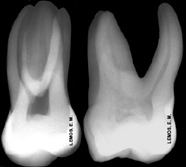

Características radiográficas do 1º. MS - 26, com incidência orto-radial |

Tomada radiográfica com a técnica do paralelismo, com auxílio do posicionador radiográfico. Desta forma, as distorções são minimizadas. |

Com relação ao irrompimento, entre 6 e 7 anos e término da rizogênese entre 9 e 10 anos. Observar o achatamento proximal na raiz mésio-vestibular: |

Os primeiros molares superiores possuem

normalmente 3 raízes, porém, a raiz mésio-vestibular pode se apresentar com 1 (40%) ou 2 (60%) canais, devido o achatamento proximal,

similar o que acontece nos segundos pré-molares superiores, segundo a média

dos autores - Hess, 1924; Pineda & Kuttler, 1972; De Deus, 1992: |